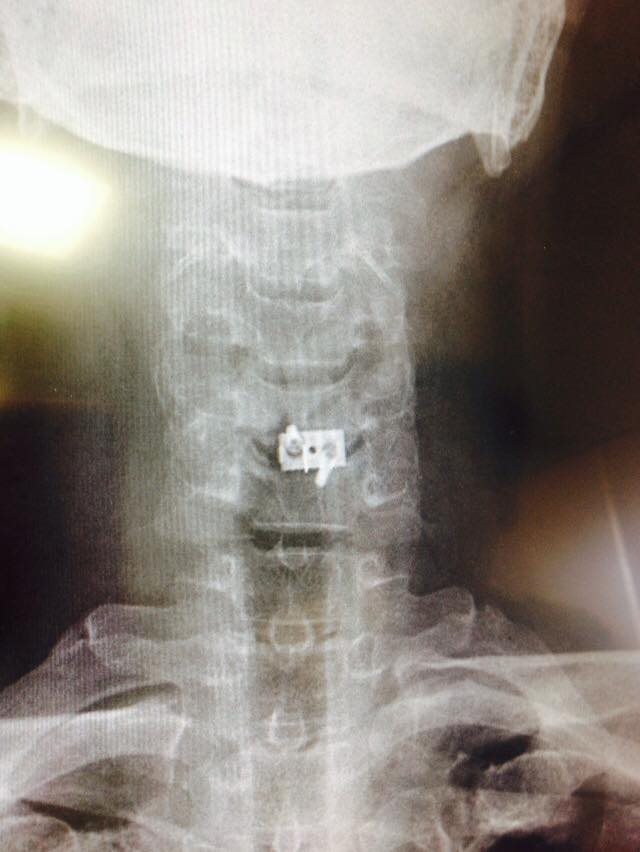

11050861_849659838443938_523163075864166819_n.jpg

11150839_849659771777278_1383166084844027666_n.jpg

11263953_849659701777285_8073529659694470784_n (1).jpg

ざっとこんな感じ(笑)

さてどれくらい腕の力と感覚戻るかなぁ~

それより左の握力関連が辛いなぁ

クラッチ握れるかな?